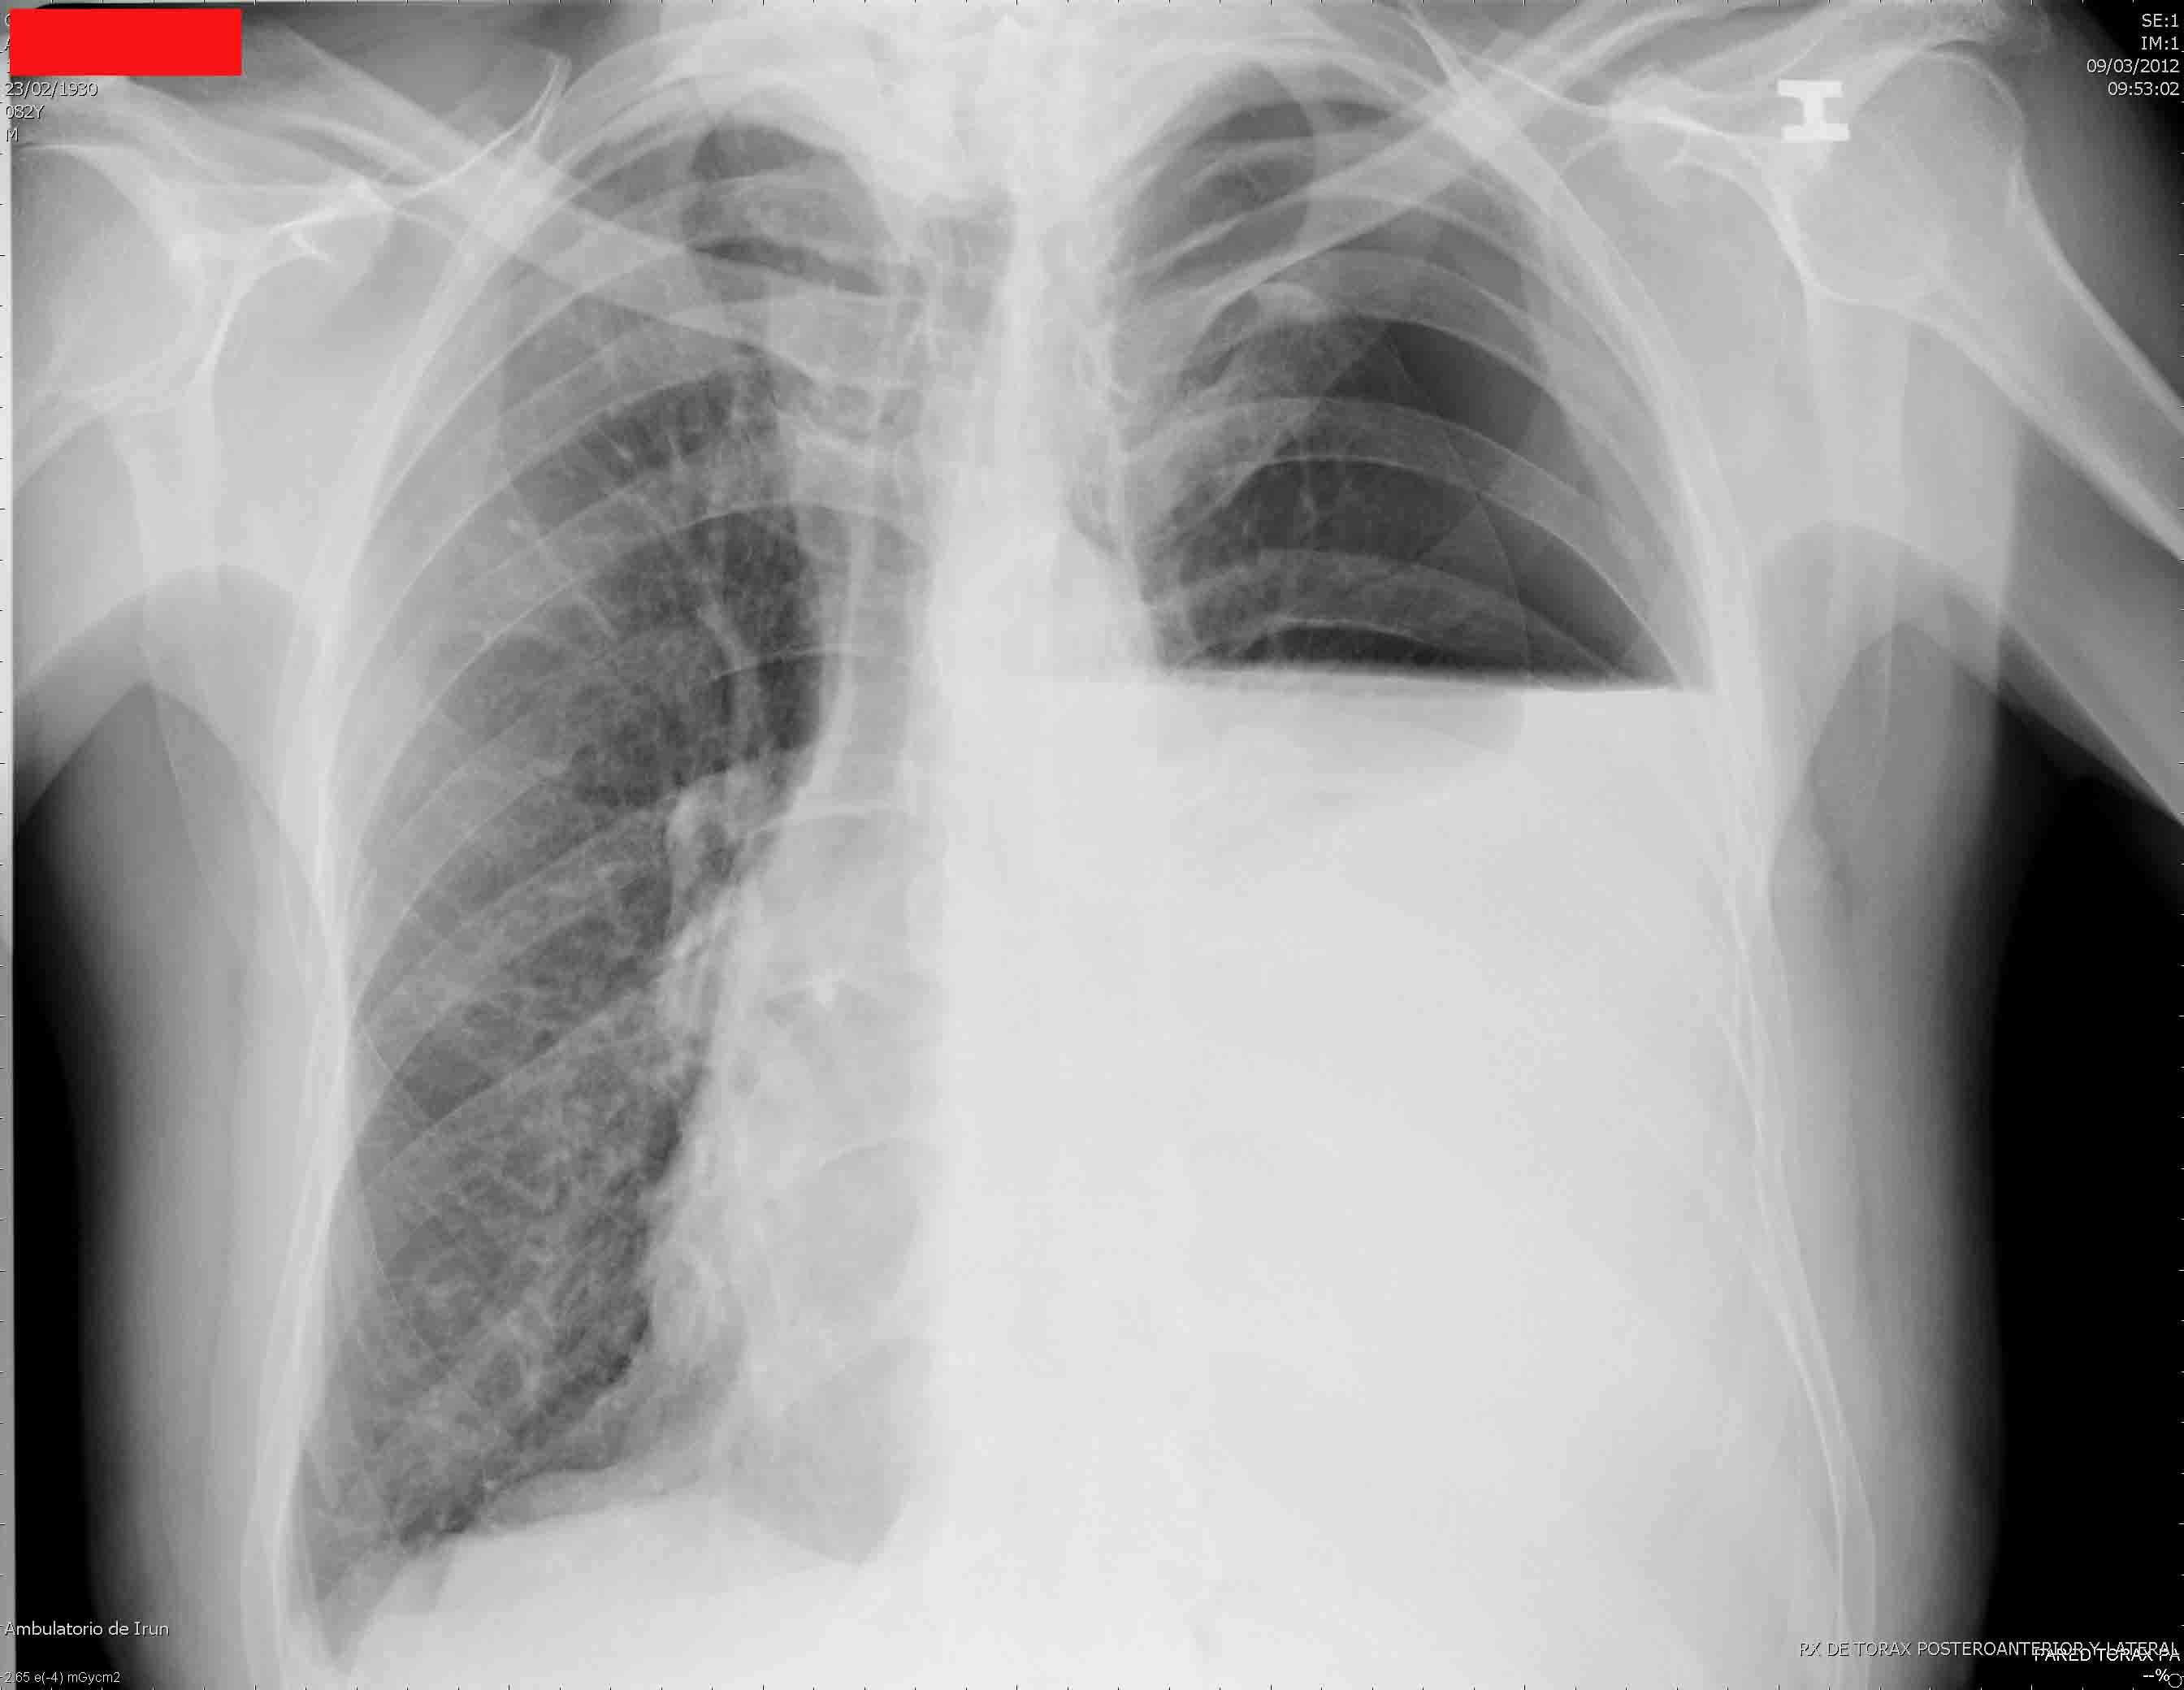

- La acumulación de líquido en la cavidad pleural puede ser pequeña (500-1000 ml), mediana más de 1500 ml; o grande más de 3000 ml; puede ser libre o enquistado; y finalmente, puede ser un trasudado (hidrotórax), un exudado serofibrinoso (pleuresía), un exudado purulento (empiema) o sangre pura (hemotórax). La sinología va a depender en gran parte de estas variables pero, tomando como ejemplo un derrame pleural libre y de más que mediano volumen, tendremos:

La curva de Ellis-Damoiseau es una línea de concavidad superior que se obtiene por percusión o Rx, e indica el límite de un derrame pleural.